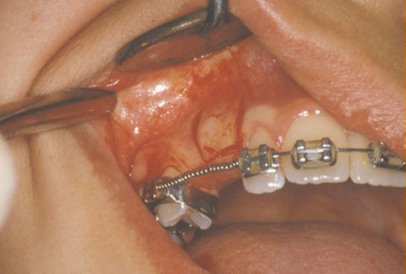

In a simple surgical procedure performed in the surgeon’s office, the gum on top of the impacted tooth will be lifted up to expose the hidden tooth underneath. If there is a baby tooth present, it will be removed at the same time. Once the tooth is exposed, the oral surgeon will bond an orthodontic bracket to the exposed tooth. The bracket will have a miniature gold chain attached to it. The oral surgeon will guide the chain back to the orthodontic arch wire where it will be temporarily attached. Sometimes the surgeon will leave the exposed impacted tooth completely uncovered by suturing the gum up high above the tooth or making a window in the gum covering the tooth (on selected cases located on the roof of the mouth). Most of the time, the gum will be returned to its original location and sutured back with only the chain remaining visible as it exits a small hole in the gum.

Shortly after surgery (same day-14 days) the patient will return to the orthodontist. A rubber band will be attached to the chain to put a light eruptive pulling force on the impacted tooth. This will begin the process of moving the tooth into its proper place in the dental arch. This is a carefully controlled, slow process that may take up to a full year to complete. Remember, the goal is to erupt the impacted tooth and not to extract it! Once the tooth is moved into the arch in its final position, the gum around it will be evaluated to make sure it is sufficiently strong and healthy to last for a lifetime of chewing and tooth brushing. In some circumstances, especially those where the tooth had to be moved a long distance, there may be some minor “gum surgery” required to add bulk to the gum tissue over the relocated tooth so it remains healthy during normal function. Your dentist or orthodontist will explain this situation to you if it applies to your specific situation.